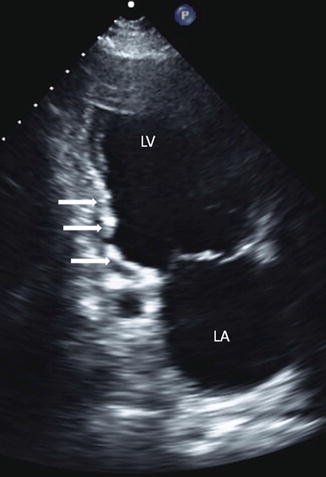

The coronary artery views obtained with epicardial imaging are dependent on the position and angulation of the probe on the heart. RECENT FINDINGS The high temporal and spatial resolution of tissue Doppler and strain rate imaging permit. Coronary arterial disease CAD constitutes the main cause of morbid-mortality in the modern world.

Echocardiography is a versatile imaging modality for the management of patients with chest pain and assessment of left ventricular systolic function diastolic function and even myocardial and coronary perfusion and is therefore useful in the diagnosis and triage of patients with acute chest. Lecture series Clinical Echocardiography. Echocardiography is the initial modality employed in the assessment of proximal coronary arteries in children Video 1. Detection of coronary artery lesions CALs at initial echocardiography can aid in diagnosing Kawasaki disease KD and inform primary adjunctive treatments. Coronary arterial disease CAD constitutes the main cause of morbid-mortality in the modern world. This study investigated the diagnostic role of layer-specific analysis using 2-dimensional speckle-tracking echocardiography STE during DSE. 1 However echo images may be sub-optimal in older patients with high body mass indices. Echocardiography in Coronary Artery Disease inproceedingsGlobits2000EchocardiographyIC titleEchocardiography in Coronary Artery Disease authorS. Coronary artery lesions prevalence at initial echocardiography consistently increased after the fifth day of illness and was higher in patients with Kawasaki disease aged 0 to 5 months and 60 months compared with those at intermediate months of age describing a Ushape trend.